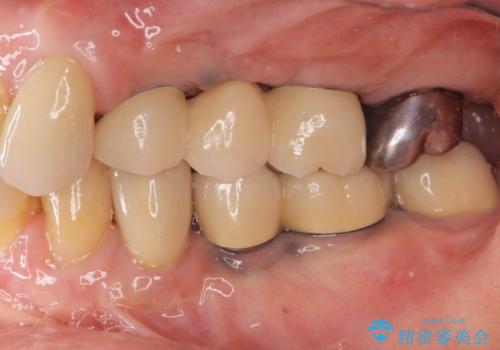

インプラント2本で3本分の咬合機能を回復することができました。(インプラントブリッジ治療)